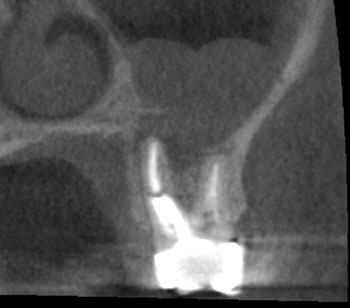

Fig. 4: Recall CBCT.

The patient returned in three months, when resolution of symptoms, healing of the deep probing defect and bone regeneration were confirmed. The tooth was obturated, and a foundational restoration was placed before the rubber dam was removed. Fourteen years of follow-up confirmed long-term periradicular health. The amount of appreciation and gratitude that this patient expressed reminds us that each individual tooth demands our best efforts.